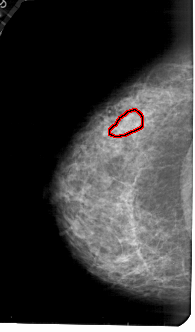

A_1777_1.RIGHT_CC

RIGHT_CC LINES 5251 PIXELS_PER_LINE 2971 BITS_PER_PIXEL 12 RESOLUTION 43.5 NON_OVERLAY

FILE: A_1777_1.LEFT_CC.OVERLAY

TOTAL_ABNORMALITIES 1

ABNORMALITY 1

LESION_TYPE MASS SHAPE ARCHITECTURAL_DISTORTION MARGINS ILL_DEFINED

ASSESSMENT 4

SUBTLETY 2

PATHOLOGY BENIGN

TOTAL_OUTLINES 1

BOUNDARY